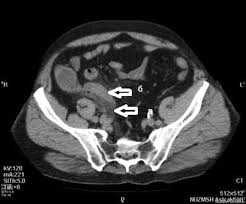

УЗИ диагностику проводят с целью уточнения места расположения и размеров абсцесса. Гнойник определяется как образование пониженной плотности неправильной формы, в просвете которого может быть виден гной.